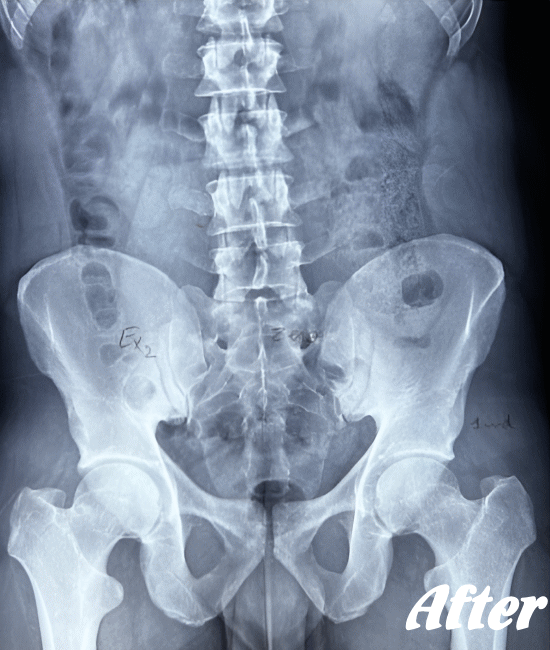

仙腸関節自体はごくわずかな動きしかありませんので、レントゲンやCT、MRIなどでは画像診断で判別することが難しいと言われています。

したがって、画像検査が難しいため、仙腸関節障害の診断は、症状経過と仙腸関節部の圧迫テストで診断されます。

HALOカイロプラクティック☆平和島整体院では、仙腸関節の動きやズレを回復させることを第一に考慮した施術を行っています。たとえ、足や肩の痛みやしびれが主訴であっても、仙腸関節を正しい状態に戻すことから施術を始めています。

仙腸関節障害による痛みやしびれは、仙腸関節を正しい位置に戻しても、その場ですぐに痛みやしびれが取れるわけではありません。軽度であれば、その場で回復しますが、重症になればなるほど、一か月程度はかかると考えて下さい。

仙腸関節、股関節、脊柱を特に集中して解剖学的に正しい位置へと戻す施術になります。HALOカイロプラクティック☆平和島整体院では、医療機関でも用いられているAKA療法も取り入れて施術しています。